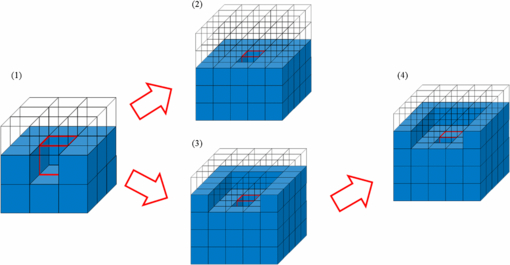

After determining the voxel resolution, the masses of the individual organs and tissues were also adjusted to the reference Korean data. In the development of the HDRK-Man, the organs and tissues had been adjusted on 2D slice images using Photoshop 7.0TM's Inner Grow and Outer Grow functions. Due to the fact that the boundary voxels were only changed in the transversal direction, some organs (e.g. the spleen) were significantly deformed in appearance. In order to avoid this problem, in the present study, a 3D volume adjustment program was developed for boundary voxel change in 3D space. Checking the smoothness of an organ surface around a boundary voxel, the program decides boundary voxels to be changed (as shown in figures 3 and 4) in order to make an organ shape as smooth as possible. Conflicts such as organ overlap could be detected by the program and resolved manually. The program not only obviated a great amount of repetitive work, but also enabled closer matching of organ and tissue masses to the reference Korean data.

Standard image High-resolution imageFigure 4. Procedures for increasing an organ volume in the 3D volume adjustment program.